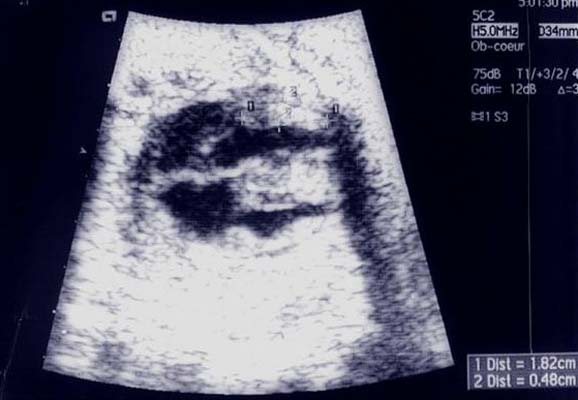

Rhabdomyome